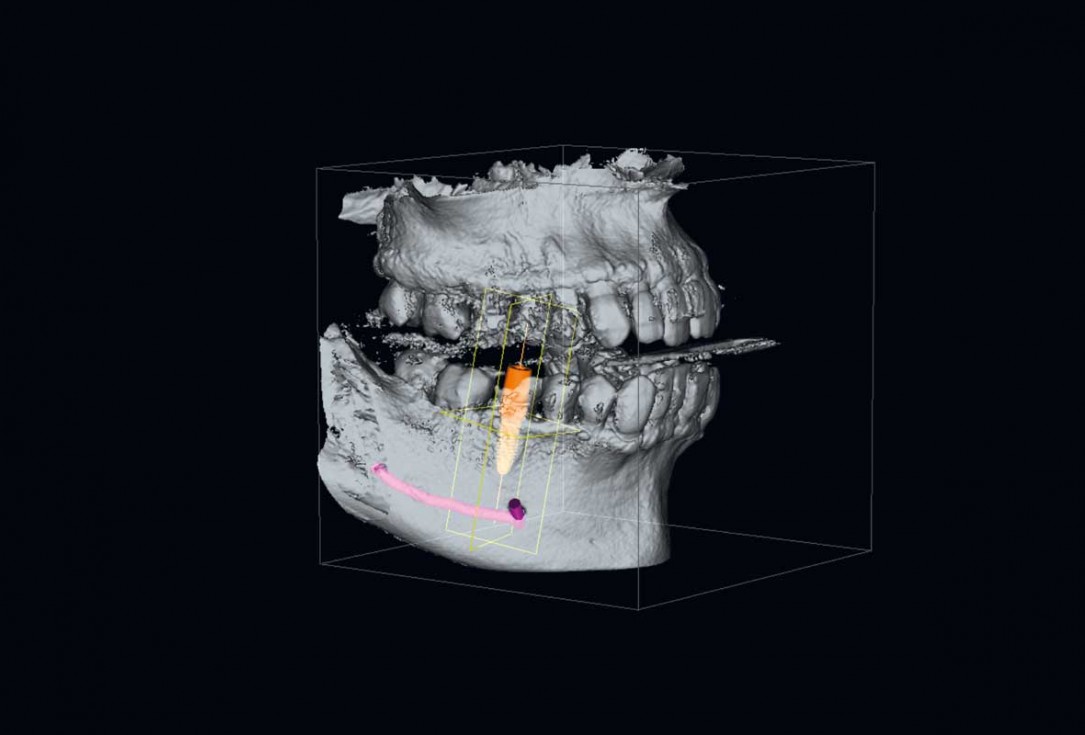

02/25 - Planning of an implant supported restoration of tooth 46Immediate implant placement and peri-implant bone augmentation with cerabone® plus - Dr. R. Block Veras